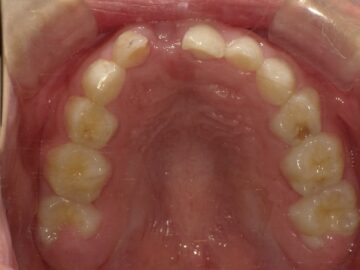

第1期治療(3~10歳)から小児矯正を治療開始できれば、第2期治療(中学~成人)から矯正治療を開始する場合と比較してみても、治療期間を短縮できるという考え方もあります。永久歯が生え揃うスペースを確保しながら顎の成長もコントロールしていくことができますので、大人になってからの矯正治療よりも短期間で終わることが多いです。もしくは、大人になってからの矯正治療が不要となる可能性もあります。

上顎の骨には繋ぎ目が存在しており、そこで左右二つの骨に分かれています。急速拡大装置を上顎に固定して装置の中央にあるネジを回すことで繋ぎ目を広げ、徐々に上顎の骨の変えていきます。そうすることで、顎の骨が正しい形に成長していくよう促され、永久歯を正しい位置で生えるように誘導できます。

上顎の拡大と下顎の歯の調整が進むと、機能的矯正装置であるアクチバトール(FKO)という装置を使用します。アクチバトール(FKO)は着脱式の矯正装置で、下顎を適切な位置へ誘導します。 顎の位置、形態が改善し、舌、口唇の位置、使い方が改善すれば、自然に歯の位置が変わって歯が綺麗に並ぶようになります。